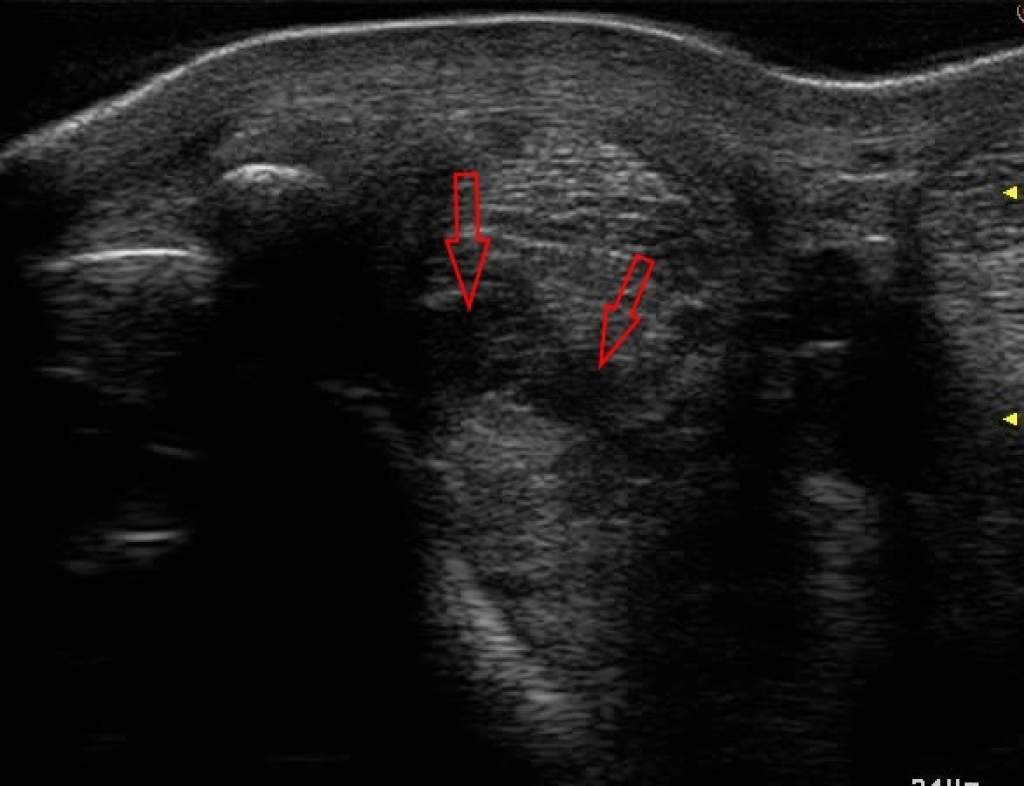

Niet alle peesblessures zullen echter optimaal profijt hebben van stamceltherapie. Met name vrij recente, 1 tot 4 weken oude, blessures komen in aanmerking voor stamcel therapie. Hoe ouder de blessure is des te minder invloed we nog kunnen uitoefenen op het herstelproces. Verder is ook het formaat en de locatie van de blessure een belangrijke factor die van grote invloed is op het effect van stamcel therapie. Bij hele kleine blessures, of blessures aan de buitenrand van een pees, kan stamceltherapie zeker het herstel stimuleren. Alleen zal het effect minder groot zijn dan bij een grotere blessure in het hart van een pees. Bij een peesblessure in een slijmbeurs is het vaak ook mogelijk om de stamcellen in de slijmbeurs te injecteren om het herstel van de pees te bevorderen.

Dwarsdoorsnede van een blessure in een tussenpees tak.

Bij een gewrichtsprobleem injecteren we de stamcellen in het gewricht net zoals bij een gewrichtsinjectie. Bij peesblessures injecteren we de stamcellen onder echografische begeleiding in de blessure, zo weten we zeker dat ze op de juiste plek terecht komen. Veelal zullen we voor dit soort injecties het paard sederen en eventueel lokaal verdoven zodat deze goed stilstaat.